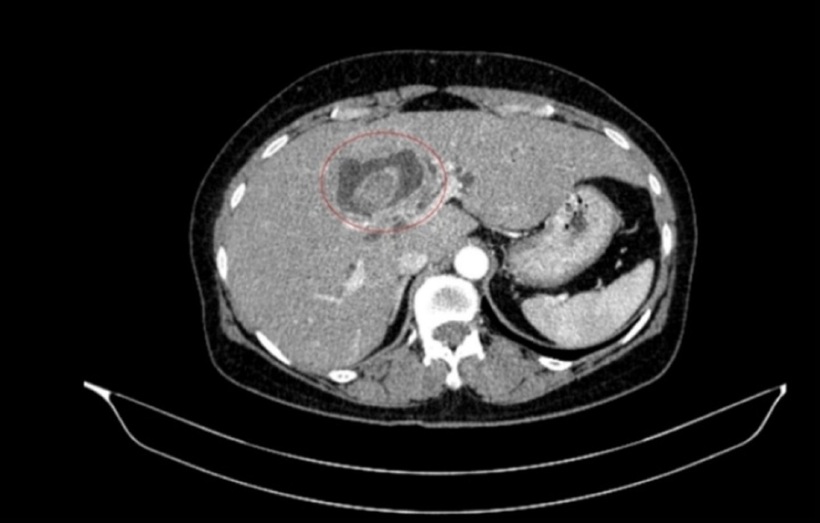

Sỏi đường mật tạo ổ áp xe gan - đường mật gan trái (vòng tròn màu đỏ). Ảnh: VTC News.

Sau hội chẩn đa chuyên khoa, các bác sĩ xác định bệnh nhân mắc đồng thời hai ung thư nguyên phát, thay vì một khối u di căn. Cụ thể, ung thư đại tràng phải ở giai đoạn sớm, chưa di căn hạch, trong khi ung thư đường mật trong gan đã ở giai đoạn tiến triển, có xâm lấn và di căn hạch.